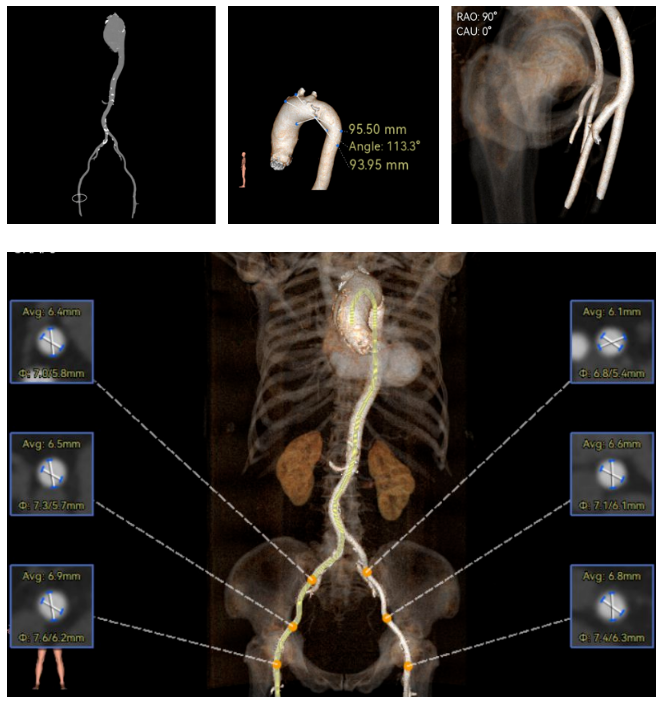

修建成教授 南方医科大学南方医院(点击查看专家详细简历) 直面瓣膜衰败,选对每一步护心路:前不久的ESC会议重磅发布瓣膜指南更新,将TAVR的患者年龄下调到70岁,且整体治疗理念迈向终身管理。该患者经历过一次外科手术,在人生70岁的当口,因生物瓣衰败再度面临 “心” 之困境,选择总是人生的一个重要课题,患者需要更微创的疗法、更耐久的瓣膜,医学的进步都是在主动探索中往前推进的,我们遵从患者的选择,不再被动应对衰败,而是主动定义瓣膜生命周期的边界。 手术一切按照既定的预演完成,术后患者情况良好,这不仅是一台手术的成功,更是将复杂瓣膜治疗推向 “精准化、耐久化” 新境序章,从瓣膜释放的瞬时血流动力学到远期抗钙化性能的预判,每一个参数都在诉说对长效生存的敬畏! 崔凯教授 南方医科大学南方医院(点击查看专家详细简历) 万千临床难题,唯提纲挈领方得始终:生物瓣衰败、心脏腔室小,这些问题都给手术添了不少难点。我始终觉得,需根据患者情况定手术方案,选择最合适的器械,综合考量:全新上市的预装干瓣开启了瓣膜心时代,预装技术让瓣膜装配标准化,规避了装载可能存在的肉眼不可见的损伤,干式储存技术规避了传统湿瓣的储存条件的钙化源头。可以说,为瓣膜的耐久性本身又增添了砝码。 对于衰败后的70岁患者,需要考量其长期耐久性问题,全新的产品需提前熟悉其产品特性;实践创新是心里装着对生命的敬畏,才能在复杂手术里找到办法。手术刀处理的不只是病,更是在跟时间赛跑,帮患者找希望。我们始终在找能让患者长期好好活下去的最好办法! 患者病史 现病史:患者近1月余前开始出现活动后胸闷、气促,爬楼、快走即可出现,休息后数分钟可缓解,至我院查心脏超声,提示:主动脉瓣生物瓣置换术后;主动脉瓣位生物瓣前向血流速度增快;左房增大,室间隔与左室后壁增厚,左室舒张功能降低,右房、右室内起博器电极线存留,二尖瓣返流轻中度,三尖瓣返流轻中度,肺动脉高压,心包积液(微量) 既往史:平素身体一般,有高血压1年,规律服用氨氯地平降压,有风湿性心脏病史,2011年行主动脉瓣生物瓣置换术;2011年植入双枪起搏器,2019年更换起搏器电池 超声提示: 主动脉瓣生物瓣置换术后;主动脉瓣位生物瓣前向血流速度增快,提示狭窄 左房增大,室间隔增厚,升主动脉增宽 右房、右室内起搏器电极线存留 三尖瓣反流(中度)二尖瓣反流(轻度) 肺动脉高压 左室射血分数正常 术前CT 生物瓣衰败ViV,原瓣膜内径19mm,LVOT23.9mm,靠原有框架锚定; 双侧冠脉开口高度可,窦部空间较大,VTC-SIMU:4.68,无冠脉风险;心脏角度47.2°; 心腔内径较小,心室壁无明显增厚,术中有循环崩溃可能; 右侧髂总动脉处有散在钙化,外周双侧入路无明显迂曲,双侧内径可,低分叉,主动脉弓距弓角条件良好; 手术策略:推荐右侧股动脉为主入路;生物瓣衰败ViV;球囊不预扩,22mm球囊后扩,预装可回收AV23主动脉瓣膜,瓣下5mm初始定位释放,工作位充分评估,符合释放要求后无张力释放 手术过程 最终造影 术后即刻探查超声平均跨瓣压差10mmHg。 术后患者当天下地,48小时出院 Prostyle A®预装干瓣——助力临床最优化解决方案: 1.平衡收腰:该患者生物瓣环较小,瓣膜型号需计算精准,Prostyle A 23号瓣膜平衡的收腰设计,兼顾血流动力学与冠脉安全; 2.柔顺过弓:较细的输送器尺寸+亲水涂层,在入路存在钙化的情况下,也能安全通过,过弓顺利,显著降低了血管并发症风险; 3.预装干瓣 便捷顺安:金仕生物专利抗钙化技术运用纳米技术去除组织内的细胞碎片和磷脂,封闭游离醛基,从根本上阻断了瓣膜钙化的多项因素,显著提升了瓣膜的耐久性;同时,相比较传统戊二醛保存方式,干式存储最大限度的保留心包的亲水亲油平衡,还原组织天然曲柔性,进一步保障了瓣叶开合,保证长期耐久性; · END ·